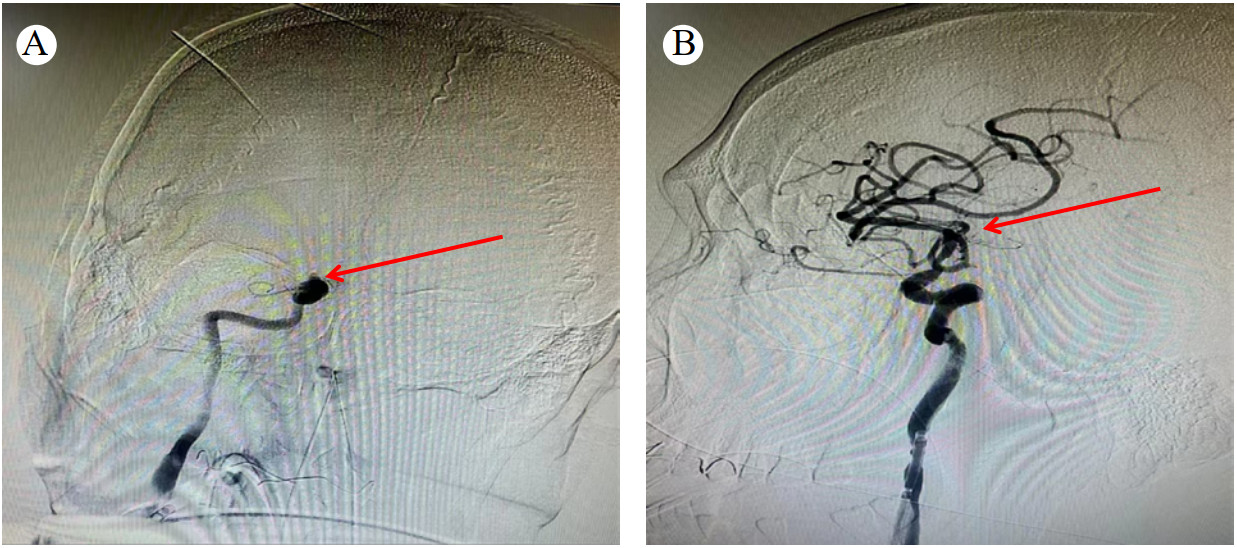

经多学科会诊决定在全麻下行急诊冠脉造影+冠状动脉介入术+脑血管造影+颅内动脉取栓术。手术开始时间为17:15,冠脉再通时间为17:22,脑血管再通时间为18:17。冠脉造影结果(图 3A):右冠近段瘤样扩张,中段闭塞,血栓负荷重,左前降支、左回旋支正常,未见右冠侧枝。给予肝素10 000单位,冠脉内血栓抽吸术后复查造影发现右冠几乎全程扩张,中段约30 mm为非扩张段,但此处急性闭塞,于右冠中段植入乐普2.5 mm×18.0 mm支架,效果满意(图 3B)。脑血管造影结果(图 4A):右侧颈内动脉末端闭塞,予取栓后血管再通(图 4B)。18:50患者转至重症医学科诊治。经鼻饲予氯吡格雷75 mg 1次/d、阿司匹林100 mg 1次/d、瑞舒伐他汀10 mg 1次/d,甘露醇125 mL静脉静注q 12 h等治疗,同时予脑保护、营养神经、维持内环境稳定等处理。

| 注:A为红色箭头为脑血管闭塞处;B为脑血管取栓术后,血管再通 图 4 患者脑血管造影 |